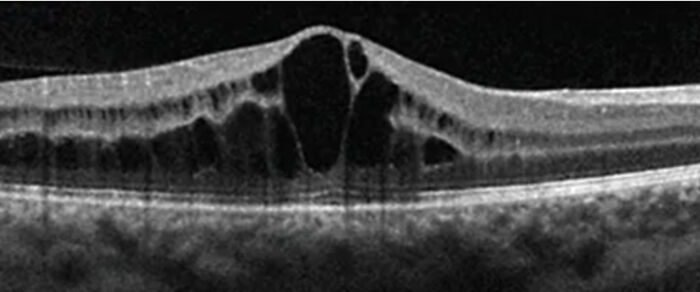

Í dag er sneiðmyndataka, OCT (Optical Coherence Tomo-graphy), lykilrannsókn í augnbotnaskoðun. OCT er myndgreiningartækni sem notar ljósbylgjur (ekki röntgen eða hljóð) til að búa til mjög nákvæmar sneiðmyndir af auganu, sérstaklega sjónhimnu, sjóntaug og gula blettinum. OCT-tæknin hefur valdið byltingu í greiningu og eftirfylgni margra augnsjúkdóma.

Mynd 3. OCT sýnir blöðru-sjónudepilsbjúg (cystoid macular edema, CME) sem getur orsakast meðal annars af sykursýki, bólgusjúkdómum í auga, bláæðalokun í sjónhimnu eða eftir augasteinaskipti.6